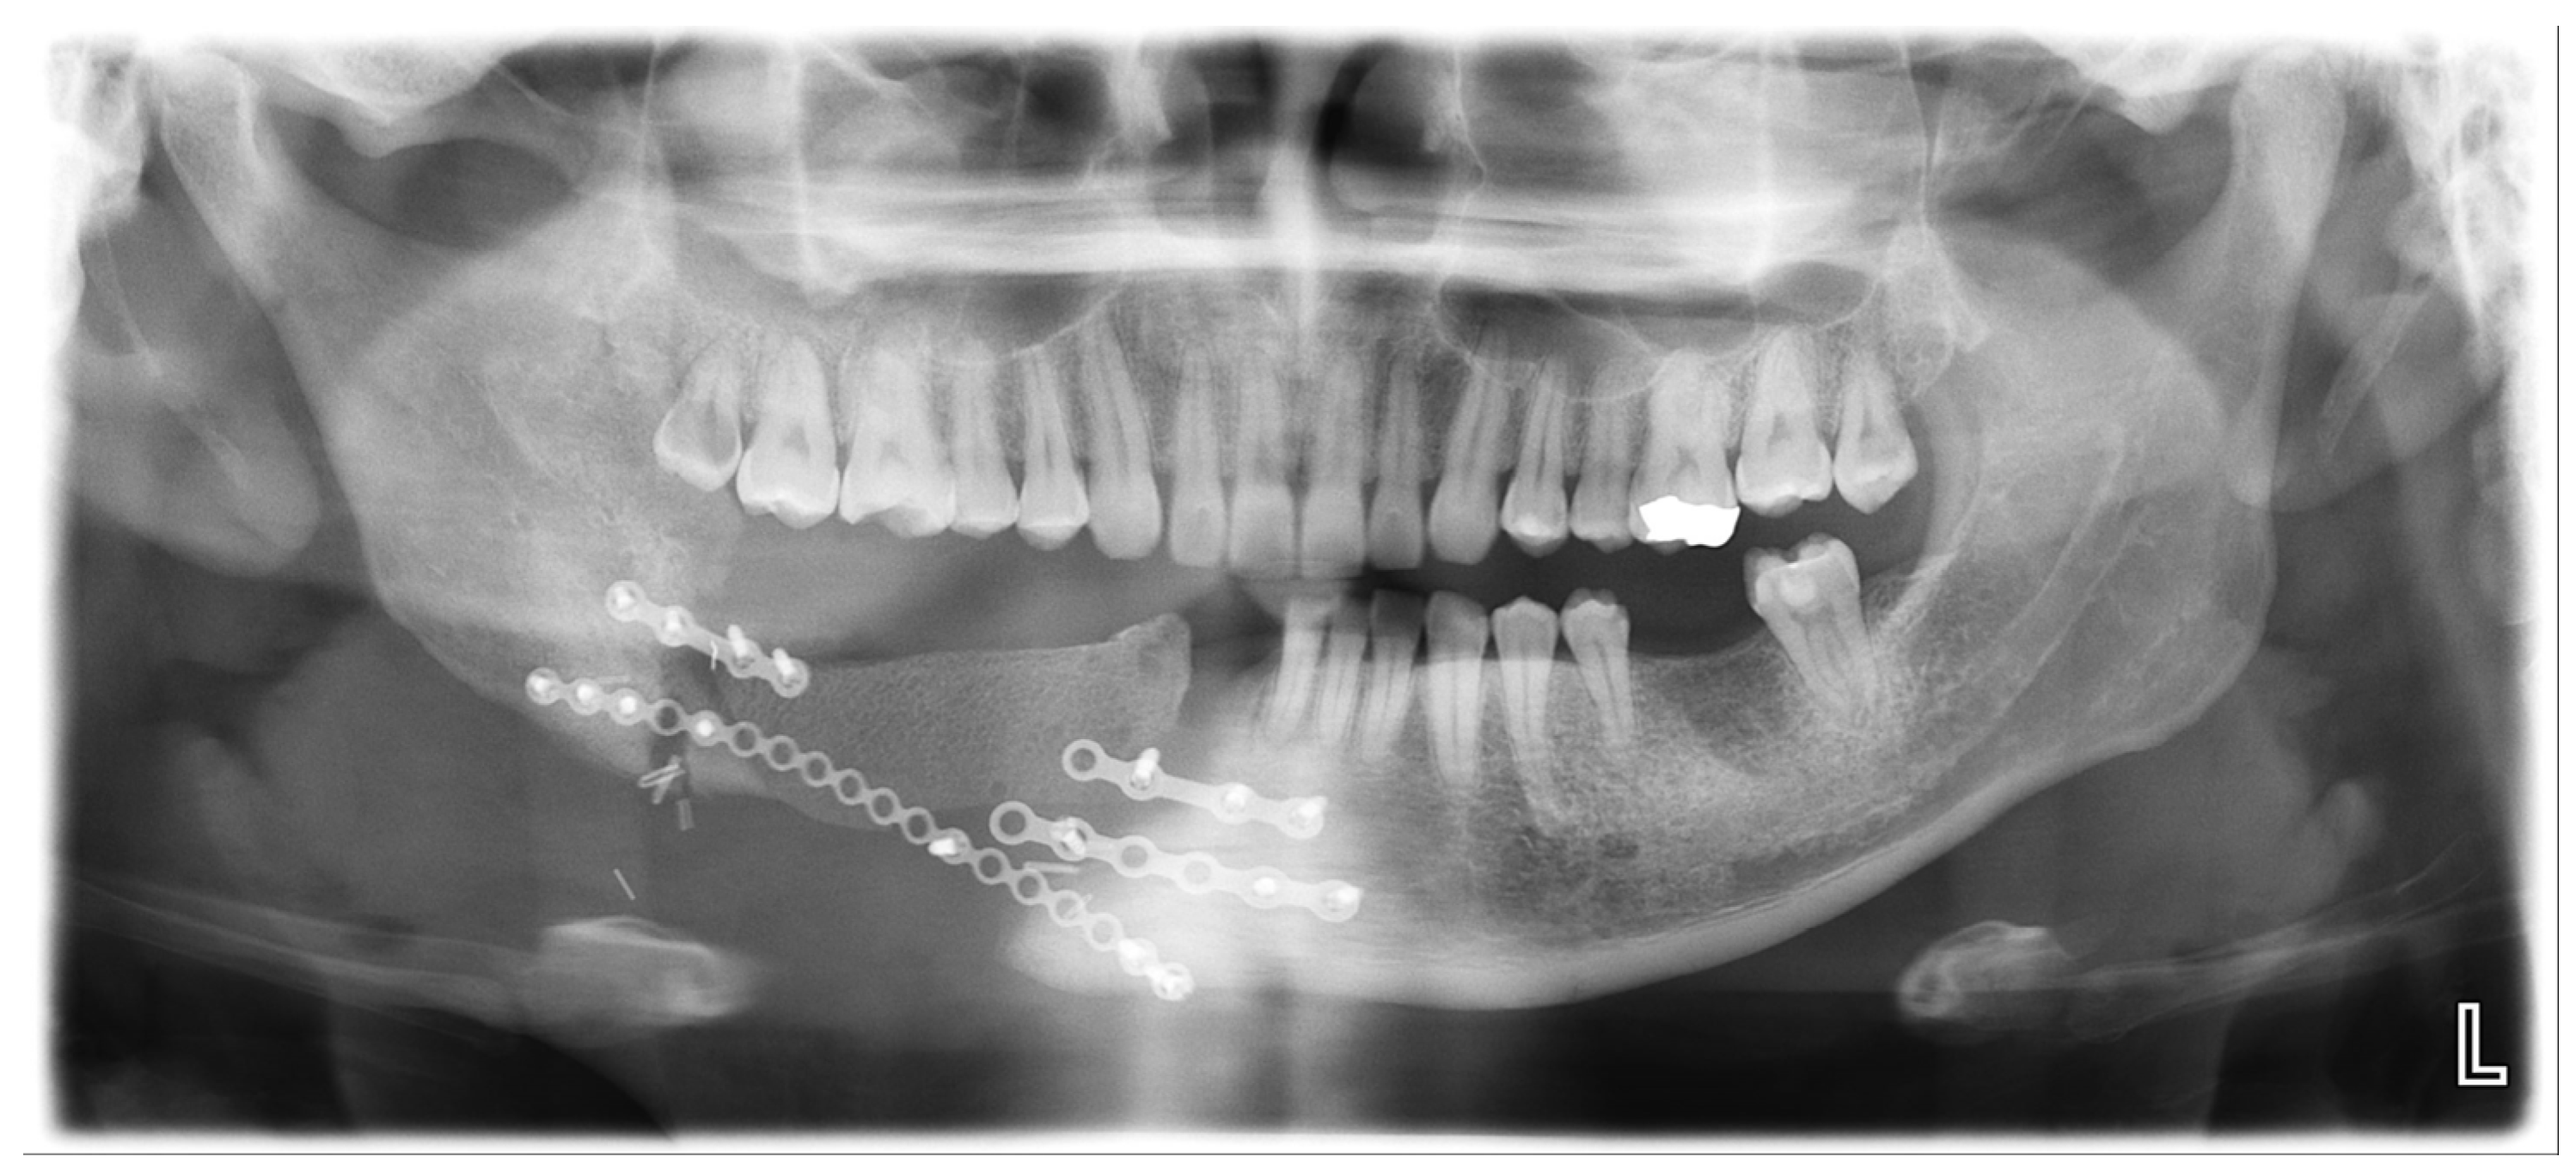

A 31-year-old male patient who underwent segmental mandibulectomy and DCIA iliac crestal free-flap reconstruction for a mandibular defect presented with plate exposure and non-union at the reconstruction site due to the infection of the reconstruction site (Figure 1).

Based on the preoperative mandibular CT from the initial lesion, the ideal mandibular form was determined (Figure 2).

Reconstruction with a bicortical DCIA flap was planned for the corresponding mandibular position (Figure 3).

Surgical guides and customized plates were manufactured according to the preoperative plan, and the reconstruction was performed using these surgical guides and customized plates (Figure 4 and Figure 5).

An accuracy analysis was performed using postoperative CT scans (Figure 6). Reconstruction of the mandible was successful, and no unusual findings were observed during the 6-month follow-up (Figure 7).

Figure 1. Preoperative panoramic radiograph.